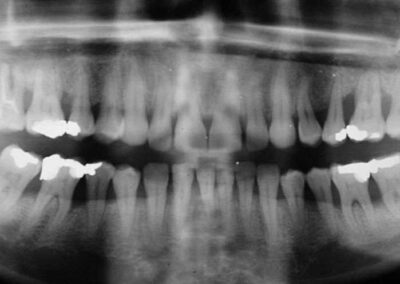

OPT aus 1992 (Klick!)

Das OPT zeigt einen Befund, bei dem der weniger Erfahrene die „Hände über dem Kopf zusammenschlagen“ würde, und der zahlreiche Implantologen zu der Bemerkung veranlassen würde, man müsse Zähne rechtzeitig ziehen, um möglichst viel Knochen für die notwendigen Implantate zu erhalten. Auffällig ist, dass der Befund im zweiten Quadranten (Zustand nach Augmentations-Versuch) deutlich schlechter ist als im ersten. Dass der Knochenbefund im OK insgesamt schlechter ist als im UK ist nicht verwunderlich. Der Knochen im OK ist eben wesentlich weniger fest, da er – im Gegensatz zum Unterkiefer- fest mit dem Schädel verbunden ist, was die Natur dazu veranlasst hat, ihn in Leichtbauweise herzustellen. Der 17 ist nicht zu halten. Sehr deutlich sind die allgemein erweiterten Parodontal-Spalten zu beobachten. Das OPT sieht aus, wie ein Zustand unmittelbar nach KFO (forcierte Zahnbewegungen) Insgesamt spricht dieser Befund für eine Kombination von Parodontitis und „Knirschen-Pressen“.

Bis auf den 18 und den 28 (keine Gegenbezahnung!!, L=0) weisen alle Zähne deutliche Lockerungsgrade auf, im Durchschnitt L=1-2, der wurzelgefüllte 17 L=sehr deutlich über 2. Die Front ist leicht protrudiert und aufgefächert bei Kontakt in Schlussbissstellung. Die Mundhygiene ist nicht schlecht, für einen solchen klinischen Zustand aber bei weitem nicht ausreichend. Trotz zweier Parodontitis-Behandlungen durch unterschiedliche Kollegen war eine Unterweisung im in solchen Fällen unabdingbaren, regelmäßigen Gebrauch von Interdentalbürstchen nach jedem Essen nicht erfolgt.. Beim Melken der Taschen ist kein Pus herauszudrücken, was die Richtigkeit der Fremddiagnose „Therapieresitente Parodontitis“ sehr unwahrscheinlich macht. Insgesamt zeigt sich eine deutliche Diskrepanz zwischen dem Grad der Entzündung, dem Knochenbefund und den Lockerungsgraden.